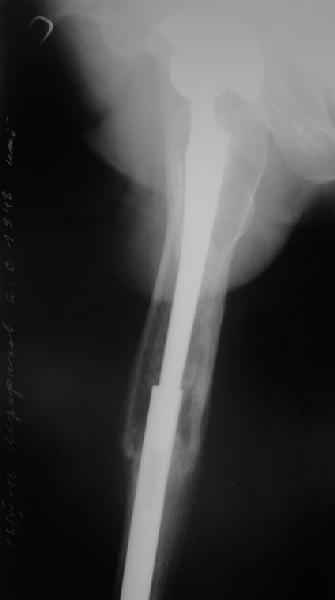

Это сплошной титановый стержень. На дистальном конце отверстия под кондуктор. На другом - канал под ножку глубиной 60 мм, стенки толщиной 2,5-3 мм. И там же продольный пропил, чтобы канал мог адаптироваться к ножке.

Дорогой Александр Николаевич! Спасибо, что держите всех нас в курсе.

Сейчас опорную нагрузку на бедро берет на себя система от бедренного компонента эндопротеза до проксимального винта в интрамедуллярном гвозде. Свидетельство тому - реакция кортикала утолщением вокруг того самого винта. Таким образом вся кость от верхушки б.вертела до проксимального винта не испытывает физиологической осевой нагрузки. Результатом этого могут стать следующие последствия друг друга не исключающие: 1) все будет хорошо до перелома опорной системы по винту(ам) или в месте соединения штифта с ножкой или еще где-либо, 2) исключенная из-под нагрузки кость будет терять в количестве и качестве, что не очень (или очень не) хорошо для возможных будущих ревизий (тьфу-тьфу!!!).

Уважаемый Александр Николаевич,

Как Вы знаете, мы имеем негативный опыт подобной операции (перелом ножки эндопротеза на месте соединения со штифтом), но тем не менее хотелось бы сказать следующее. На мой взгляд,выполняя такую фиксацию, мы становимся заложниками сохранения всей этой мегаконструкции на долгое время, если не на всю жизнь. Эта система работает уже как единое целое. Рефиксации ножки эндопротеза не произошло, при удалении гвоздя может развиться вторичная нестабильность, скорее всего со временем произойдут дистрофические изменения в кости за счет шунтирования нагрузки. Поэтому есть смысл отследить очень тщательно р-ты этих операций, прежде чем они войдут в повседневную практику, думаю что показания к ним будут весьма ограничены. Пару раз попробовали "пошалить", собрали бедро на бесцементной ножке у пожилых б-х дабы не утяжелять вмешательство. В одном случае - срослось и ножка получила стабильность, в другом - потребовалось реэндопротезирование, но со значительно меньшей травмой. т.к.бедро срослось.